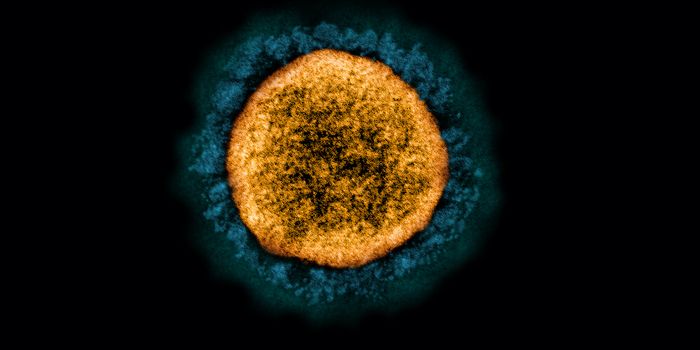

JUL 11, 2021MicrobiologyIn October 2020, what's now called the Delta variant of SARS-CoV-2 was first detected. It's now the most prevalent strai ...

NOV 01, 2021Cell & Molecular BiologyResearchers have learned a lot about the SARS-CoV-2 virus since the start of the COVID-19 pandemic. We know that he viru ...